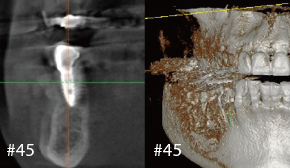

1. 술전